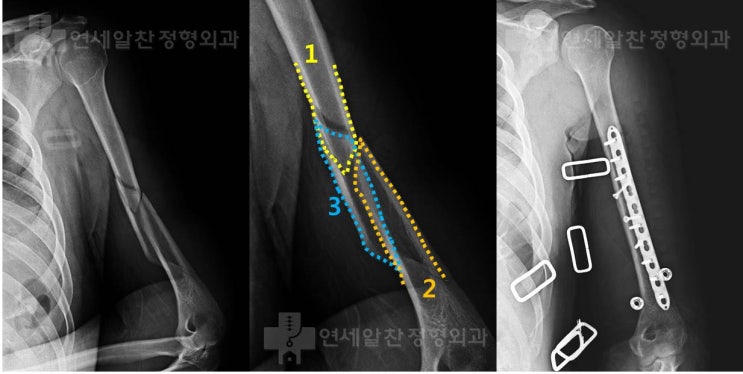

상완골 간부 복잡 골절에서 관혈적 정복술 및 금속 내고정술의 결과

29세 남자 환자로 팔이 비틀리며 넘어지면서 발생한 상완부의 통증으로 본원으로 내원하였다. 타 병원에서 ...